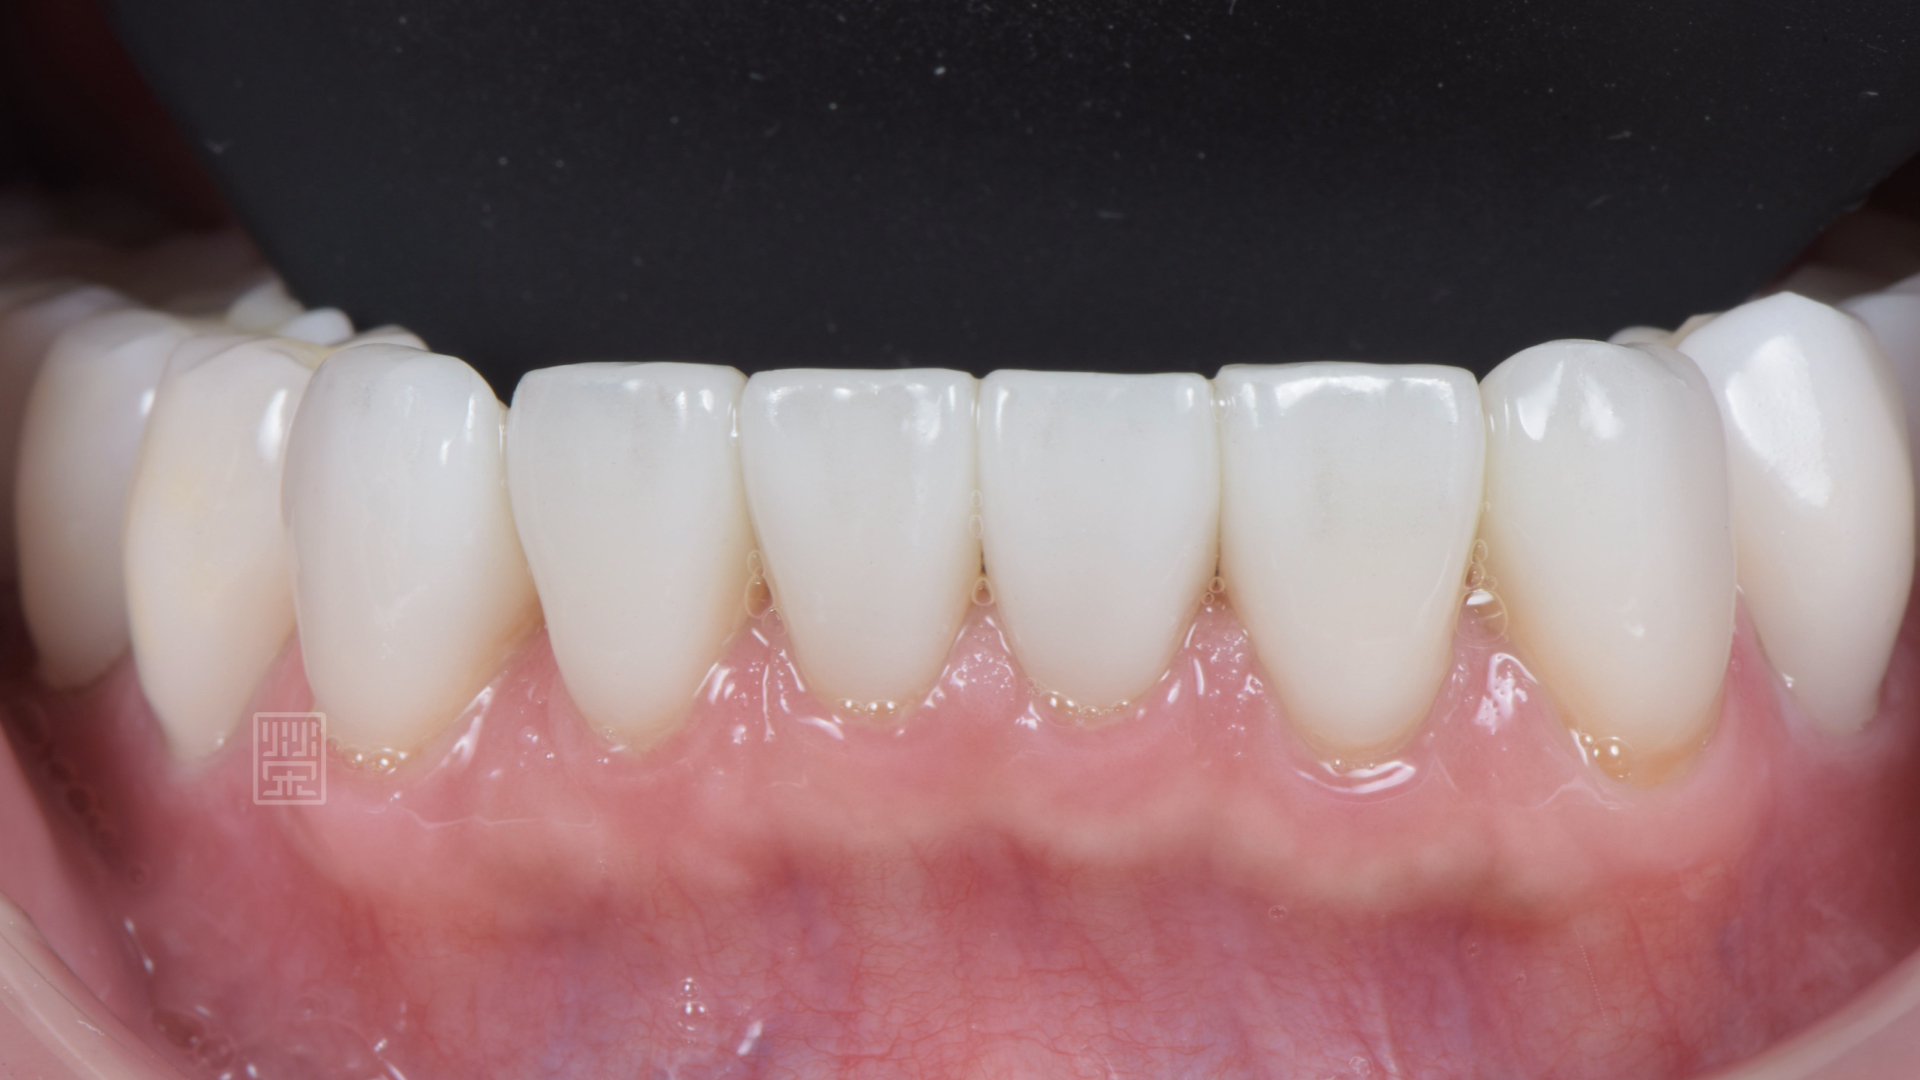

玻璃陶瓷貼片改變下顎門齒顏色與型態

全瓷贋復物完成